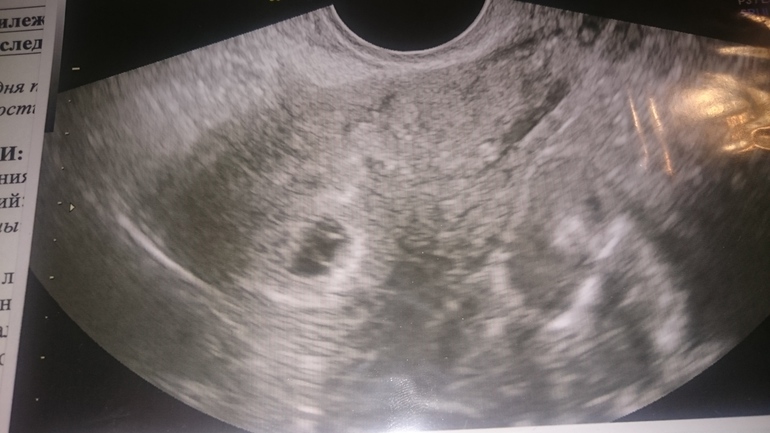

Помогите разобоаться с фото узи

Просто смотрю по фото других узи видны круглые полые шарики, и они гораздо меньше плодного яйца, а тут даже если представить что два отростка там где то замыкают, то как то сильно он большой.

Одно желтое тело. Все у вас хорошо) рановато еще для эмбриона) в 8 недель будет все понятно. Но у диди двойни сразу 2 тела.

Голову не ломайте. Подождите немного пусть подрастет. Еще от аппарата зависит и от узиста, одни видят другие не видят. Я ходила на третий день задержки и то из-за того что врач убеждала, что может быть внематочная. Хотя я знала что все там где надо. На узи что то нашли, но очень маленькое еще ничего не понятно было. Отслеживай по росту ХГЧ. И главное чтобы желтое тело было нормальных размеров, оно помогает развиваться эмбриону.